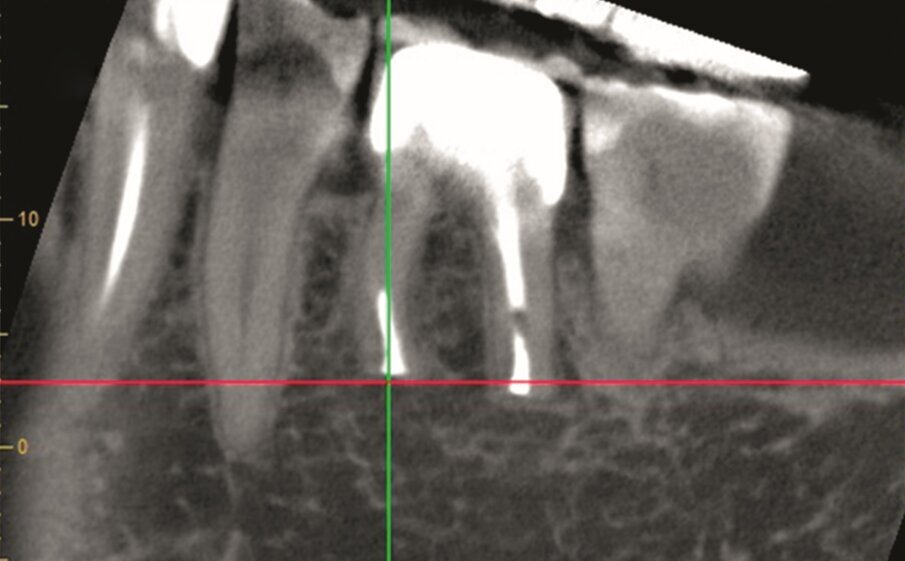

Fig. 1a–d: Pre-op CBCT scan of tooth #36. The axial (a), …

…and sagittal views (c) showed a hypo-dense zone around the apical third of the mesial and distal roots and intact cortical buccal bone.

A template that marked the limits of a cortical window to accurately reach the apical area of both roots was designed (d).

A 63 year old female patient, with a non-contributory medical history, consulted owing to moderate pain associated with her previously treated mandibular left first molar. CBCT revealed that a mesiobuccal canal had being missed during initial treatment, that the mesial and distal roots were affected by an apical lesion, and that the cortical buccal bone was intact.

Retreatment was done in two appointments, and calcium hydroxide was used as the intra-canal dressing after removing the previous filling material and cleaning and shaping three canals. After one week, root canal therapy was completed. Two months later, symptoms persisted and clinical examination revealed pain on vertical percussion; periodontal probing depth and mobility were within normal limits. CBCT revealed no signs of bone healing (Figs. 1a–c). The diagnosis for tooth #36 was previously treated symptomatic periapical periodontitis, and the treatment of choice was guided EMS.